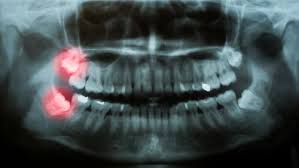

Without insurance, the typical cost of wisdom tooth extraction is rather high. If your dentist has recommended wisdom teeth removal, read on. When planning the removal of wisdom teeth, one important consideration is the position of the mandibular nerve in relation to the roots of the wisdom teeth. This is why some young adults have their wisdom teeth pulled before the teeth cause problems. Wisdom teeth do not necessarily have to be removed. Visit insider's health reference library for more advice. If these occur, your dentist is likely to recommend surgery to have them removed. Sensitivity & pain in the back of your mouth.

Patients, on the other hand, always have the option of keeping their wisdom teeth. Before your wisdom teeth are removed, your dentist will most likely refer you to an oral surgeon. Recovery may take longer if your wisdom teeth are impacted. Impacted wisdom teeth can cause problems with crowding of other teeth and even make treatment to straighten other teeth necessary. Stock up on the ice cream and movies, and prepare to reunite with the tooth fairy. Infection around the wisdom tooth or teeth. These surgeries are prevalent, and wisdom teeth recovery can take up to a week, depending on your case. Wisdom teeth symptoms can range from painless to extremely painful depending on the situation and the person. As wisdom teeth are the final ones to erupt, there is sometimes not enough space for these to fit in the jaw. Other reasons for removing wisdom teeth include: However, discomfort in other areas can also be a sign that you need them removed. Wisdom tooth infections are telltale signs you need to get your wisdom removed, and is the best wisdom tooth infection treatment. When planning the removal of wisdom teeth, one important consideration is the position of the mandibular nerve in relation to the roots of the wisdom teeth.